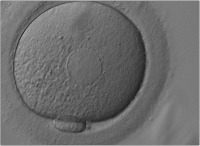

Die Bedeutung der Morphologie der Oozyte hinsichtlich ihres weiteren Entwicklungspotentials

Journal für Reproduktionsmedizin und Endokrinologie - Journal of Reproductive Medicine and Endocrinology 2006; 3 (1): 17-23 Volltext (PDF) Summary Abbildungen